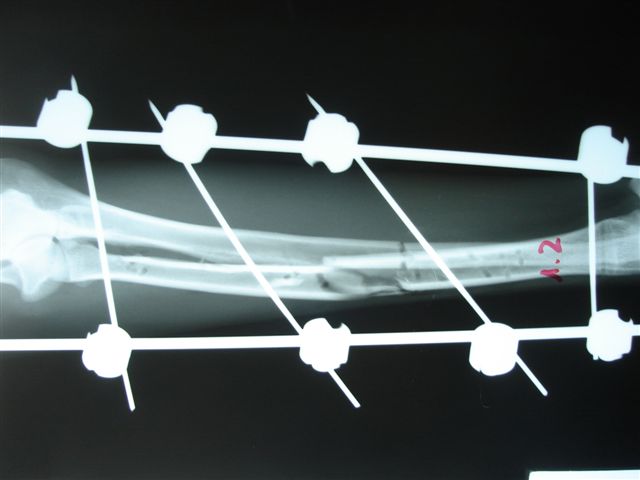

Fijación Externa en IVOT

Fijación Externa

IX CURSO BASICO DE FIJACION EXTERNA.

Casos prácticos alumnos.